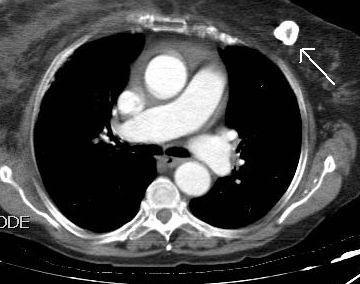

Densidad similar al músculo con estriaciones internas de grasa

Hallazgo incidental . Región infraescapular 2% de TC del tórax. Bilateral 60%.

Burt AM et al. Imaging review of lipomatous musculoskeletal lesions. SICOT J2017/ Murphey MD et al. From the archives of the AFIP: benign musculoskeletal lipomatous lesions. Radiographics. 2004